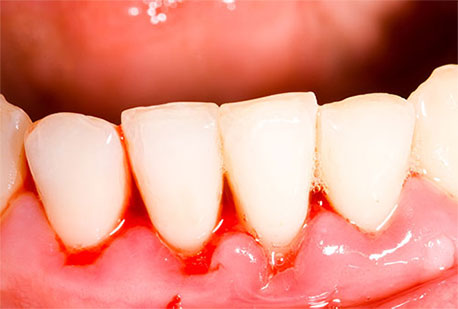

Periodontal disease is a chronic gum infection caused by plaque resulting in loss of bone support around the roots of teeth. Plaque is a thin film of bacteria that forms on teeth. Plaque converts to tartar if not cleared from teeth after 24hrs. Tartar irritates gums leaving them red, swollen and bleeding readily.

- Bleeding gums when you brush or floss

- Red, swollen, tender gums

- Gums that have receded or shrunken away from teeth

Treatment usually involves a thorough scaling and root planning to remove plaque and built up tartar, thus allowing healthy gums tissues to reattach to root surfaces of teeth. Clean surfaces of teeth must be maintained by meticulous home oral hygiene and routine check-ups and cleaning. Advances stages of periodontal disease however, may require gum surgery, grafting, and/or extractions.